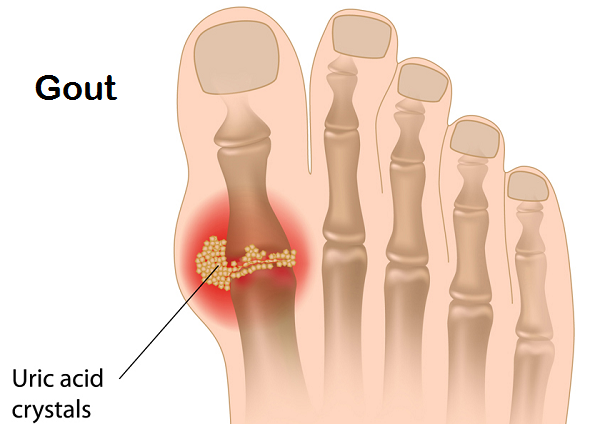

Gout:

A condition resulting from excess uric acid in blood, that may lead to formation of crystals within joints. Unlike other forms of arthritis that are more common with women, men are more prone to Gout. You may develop Gout in your big toe, ankle, feet and knees. Besides, they may appear on any other joint of our body as well.

Causes:

- High blood pressure and diabetes

- Suffering from high uric acid for long duration

- Kidney disorders wherein they don’t filter out excess uric acid in blood

- High levels of fat and cholesterol

- Obesity

- Excessive consumption of alcohol

Symptoms:

Gout symptoms show up within few hours and last for around 10 days, after which they disappear. They return in an intensified form after a short duration.

- Severe pain around the joint mostly during nights

- The symptoms come and go. This is what differentiates it from other forms of arthritis.

- Hot and tender joints to an extent that it becomes difficult to touch it gently

- Visible swelling and redness

- Shiny skin over the affected joint

- Itchy skin once the swelling disappears

- Menopause makes women susceptible to Gout